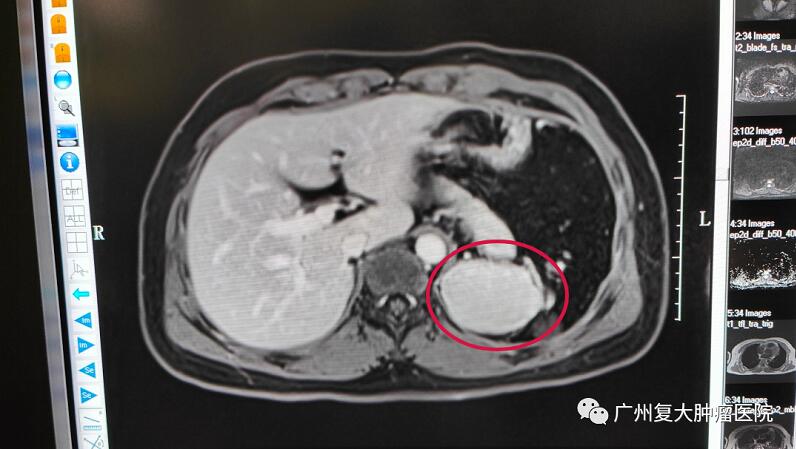

带着惴惴不安的心情,小伙子来到广州复大肿瘤医院就诊。入院后检查发现其彩超结果提示,左侧肾上腺区可见低回声肿物,边界清,内回声均匀,双肾血流灌注良好。为进一步诊断,小伙子又接受了上腹部MRI平扫+增强+DWI检查,脾脏缺如,脾脏术区可见大小约65×52×56mm团块灶,其内可见脾动静脉走行。

了解到患者几年前曾因车祸造成脾脏破裂,做过脾脏切除术,放射科李忠海主任结合影像结果及既往病史,认为该肿块并非肿瘤,而是副脾或残余脾脏代偿性增大。